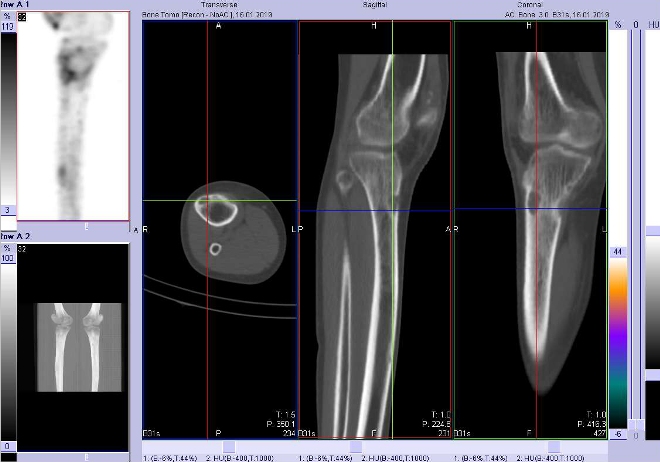

Celotělové scintigramy (obr.3) jsme provedli po podání 700 MBq

99mTc-oxidronátu (přípravek TechneScan HDP firmy Mallinckrodt Medical) na hybridní tomografické scintilační kameře Symbia T2 firmy Siemens. Vyšetření jsme doplnili o cílenou tomografickou scintigrafii (SPECT) kombinovanou s CT kolenních kloubů a přilehlé části stehenních kostí a kostí bérců

(obr. 4-11).

/ Obr. č. 4: Fúze obrazů SPECT a CT. Zaměřeno na ložisko v proximální části pravé tibie. Řez transverzální, sagitální a koronální.

/

/ Obr. č. 5: Fúze obrazů SPECT a CT. Zaměřeno na ložisko v proximální části pravé tibie. Řez transverzální, sagitální a koronální.

Popis: Tři ložiska lehce vyšší osteoblastické aktivity v pravé tibii – dvě v proximální části a třetí je v diafýze zhruba uprostřed laterálně. Tato ložiska jsou na ldCT oválného tvaru v kortikalis povrchově s výrazně sníženou denzitou (osteolytická), kortikalis je poněkud ztenčená. S velkou pravděpodobností se jedná o neosifikující fibromy.